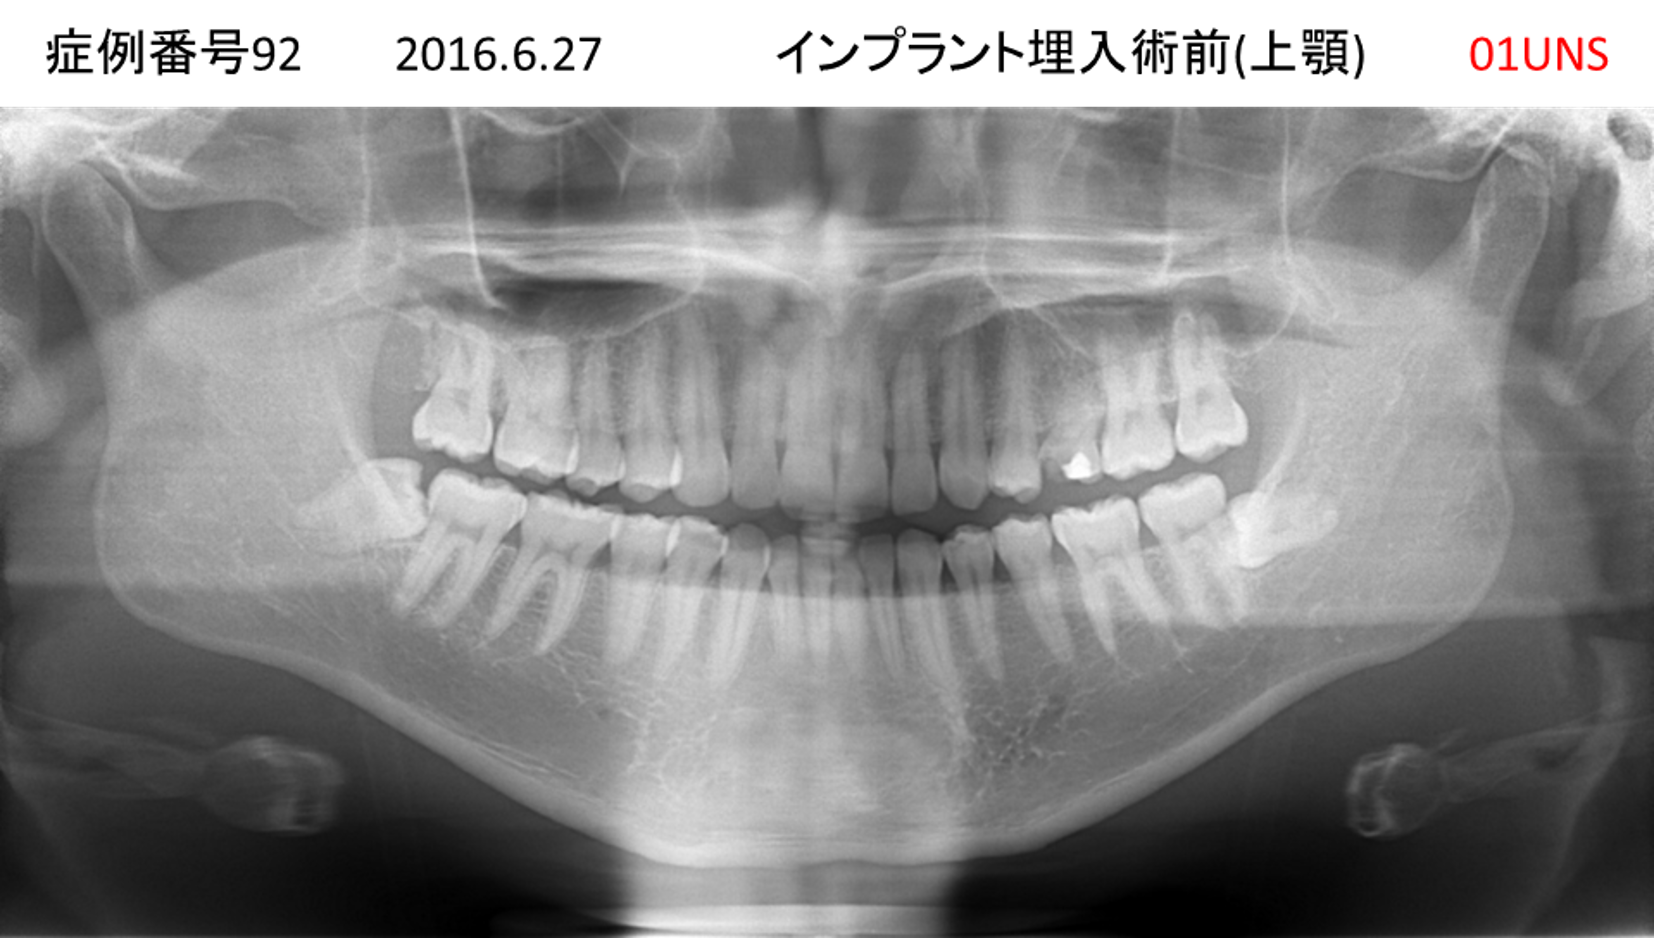

上の前歯が揺れてきてかめない患者様のインプラント症例

| 治療名称 |

インプラント |

| 治療費用 |

440万円+税 |

| 治療期間 |

6か月 |

| 患者さんの症状(主訴) |

上の前歯が揺れてきた。かめない |

| 治療内容 |

サイナスリフト、GBR、インプラント、即時荷重 |

| 治療結果 |

上の前歯の揺れが収まった。奥歯でしっかり噛める。 |

| 治療の注意点(リスク/副作用) |

インプラントが壊れたら再治療が必要 |